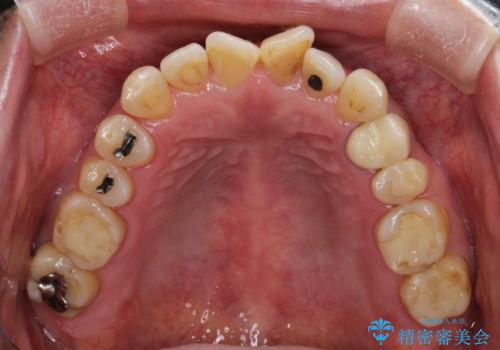

【インビザライン】前歯のガタガタを治したい

- 前歯のガタガタを主訴に来院されました。

上の歯の前突も気になってたため、奥歯の遠心移動も行いながらインビザラインにて治療を行いました。

前歯も下がり満足していただきました。

今回は奥歯の遠心移動とIPRを行って配列しています。